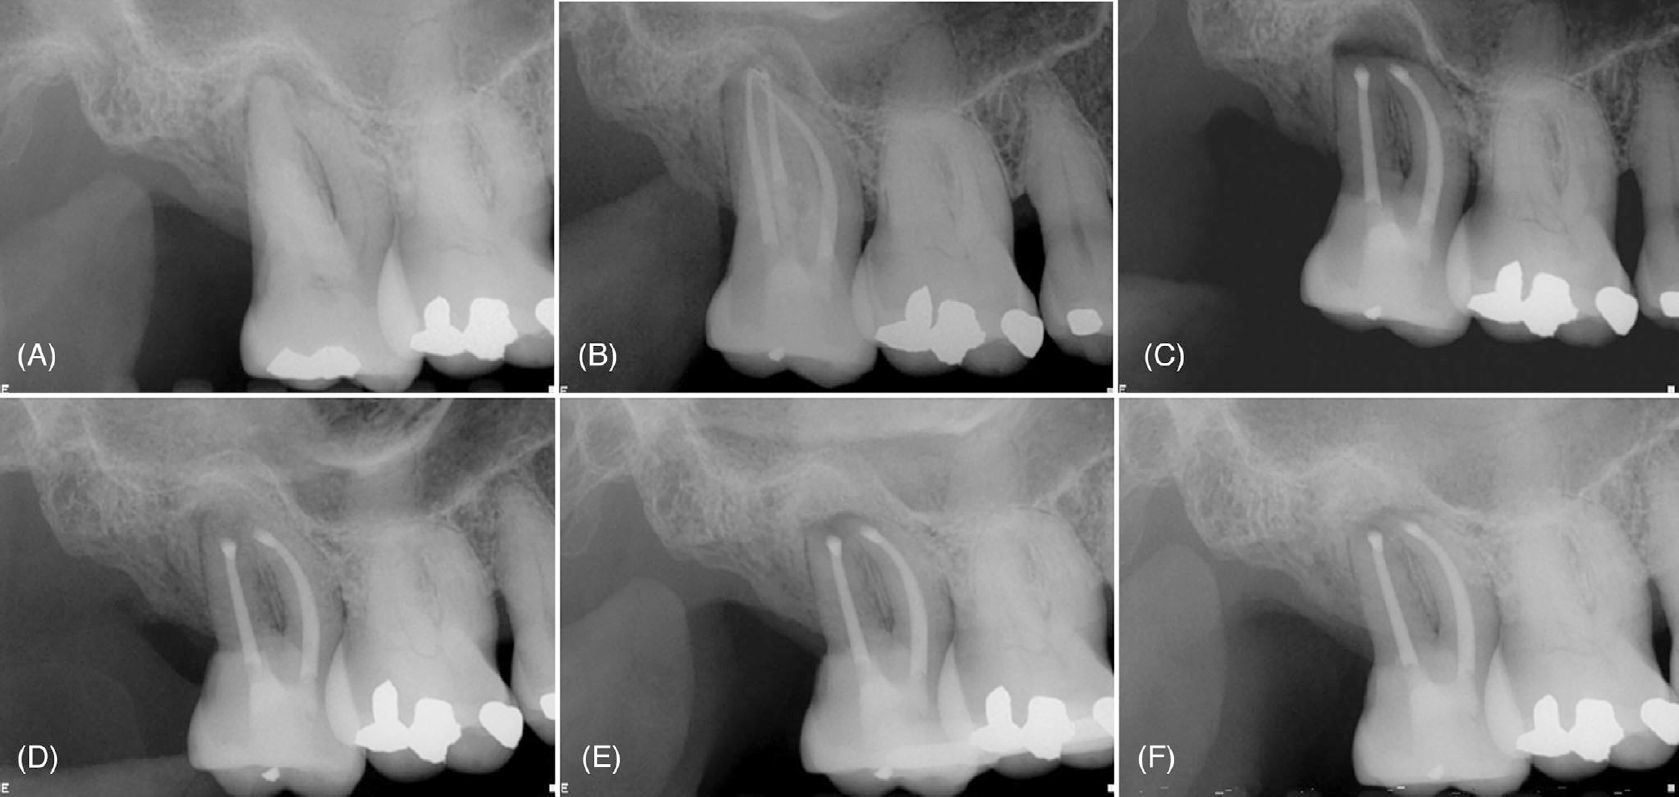

Фото 1. (A) Периапикальные рентгенограммы зуба 17 с рентгенопрозрачным очагом, окружающим корни, и (B) состояние после эндодонтического лечения корневых каналов. (C) Интраоперационная рентгенограмма после ретроградного препарирования и пломбирования щёчных каналов и полной резекции небного корня. (D) Непосредственная послеоперационная рентгенограмма после направленной костной регенерации. Рентгенограммы через 1 месяц (E) и 14 месяцев (F), демонстрирующие стабильное заживление и заполнение костного дефекта